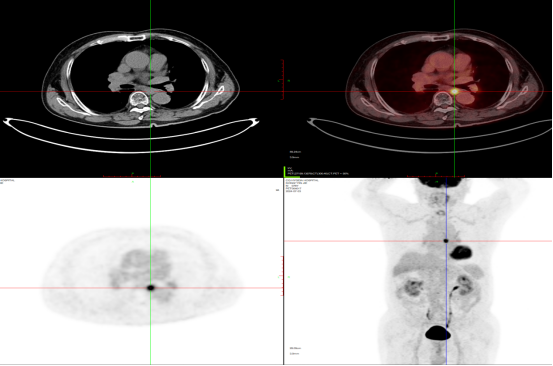

肺癌治疗后2021-9-27 2022-6-20